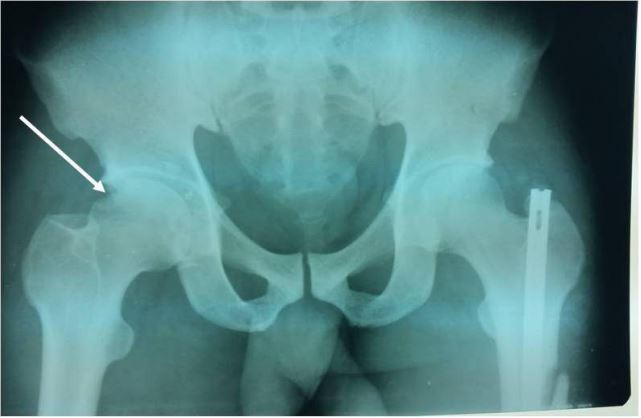

Case 1: Mr. BA was a 29-year-old patient who was hospitalized in October 2000 following a road traffic accident. He was sitting behind the driver when his right knee hit the driver’s seat. On admission, the same limb was abducted, externally rotated and flexed at the hip. An anteroposterior radiograph of the pelvis revealed a right obturator dislocation (Figure 1) associated with a left supracondylar open fracture. Treatment consisted of closed reduction. The hip was stable afterward. The left supracondylar open fracture was treated surgically. Weight bearing on the dislocated limb was authorized after 6 weeks of bed traction. Thirty nine months later, the right hip is mobile, painless and normal on plain X-rays.

Figure 1: Anteroposterior X-ray of the pelvis showing a right obturator dislocation (patient 1).

Figure 3: Anteroposterior X-ray of the pelvis showing a right obturator dislocation with an intra-articular incarcerated fragment (arrow) and a left subtrochanteric fracture (patient 3).